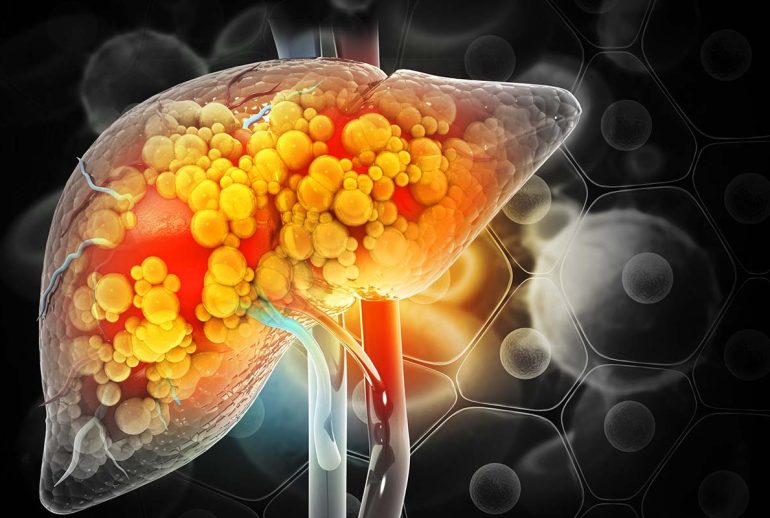

کبد چرب غیر الکلی یکی از شایعترین بیماریهای کبدی است که در سالهای اخیر توجه زیادی را به خود جلب کرده است. این بیماری با تجمع چربی در سلولهای کبدی مشخص میشود و میتواند عوارض جدی برای سلامتی به همراه داشته باشد. در این مقاله، به بررسی دقیق کبد چرب غیر الکلی، علل، علائم و روشهای درمان آن میپردازیم.

کبد چرب غیر الکلی (NAFLD) زمانی رخ میدهد که بیش از 5 درصد از سلولهای کبدی با چربی پر شوند، بدون اینکه مصرف الکل علت اصلی آن باشد. این بیماری میتواند از یک وضعیت خفیف تا شدید متغیر باشد و در صورت عدم درمان، میتواند به سیروز کبدی و حتی نارسایی کبد منجر شود.